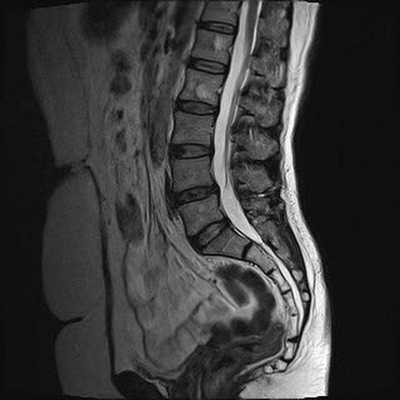

Снимок МРТ поясничного отдела позвоночника в сагиттальной проекции при остеохондрозе

МРТ позвоночника. Сагиттальная Т2-взвешенная МРТ, срединный срез поясничного отдела. Показана нумерация позвонков, измерения позвоночного канала (черная линия). Т- дуральный мешок с ярким ликвором. L- желтая связка. Sacrum - крестец. D - межпозвоночный диск. Голубым выделен остистый отросток, желтым - тело позвонка, Голубые точки - ход корешков.